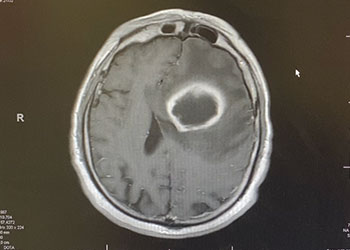

Brain:

Atypical Convexity Meningioma

Author: Jonathan L. Brisman M.D., F.A.C.S., Read More!